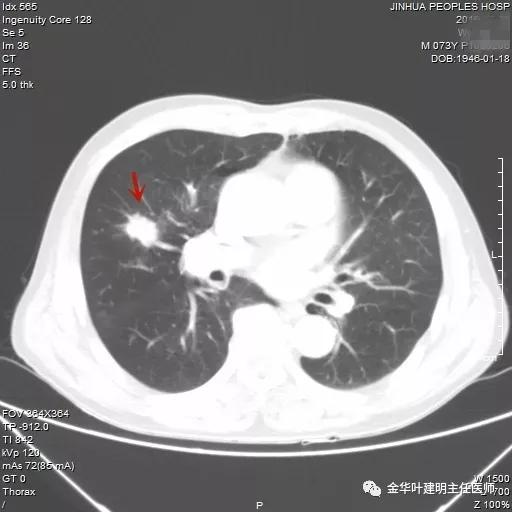

武义的吴某,今年已经73岁了,患有慢性支气管炎与肺气肿多年,每到天气转凉就要胸闷、气急及咳嗽、咳痰发作,严重时还有喘憋症状,每年都要住院1-2次。今年4月份的时候吴某又因慢支急性发作来我院呼吸内科住院。常规检查时发现右肺上叶有一实性结节,约1.5厘米大小,有毛刺及浅分叶,考虑肺癌可能性大,医生建议其行肺穿刺活检。当时图片如下: